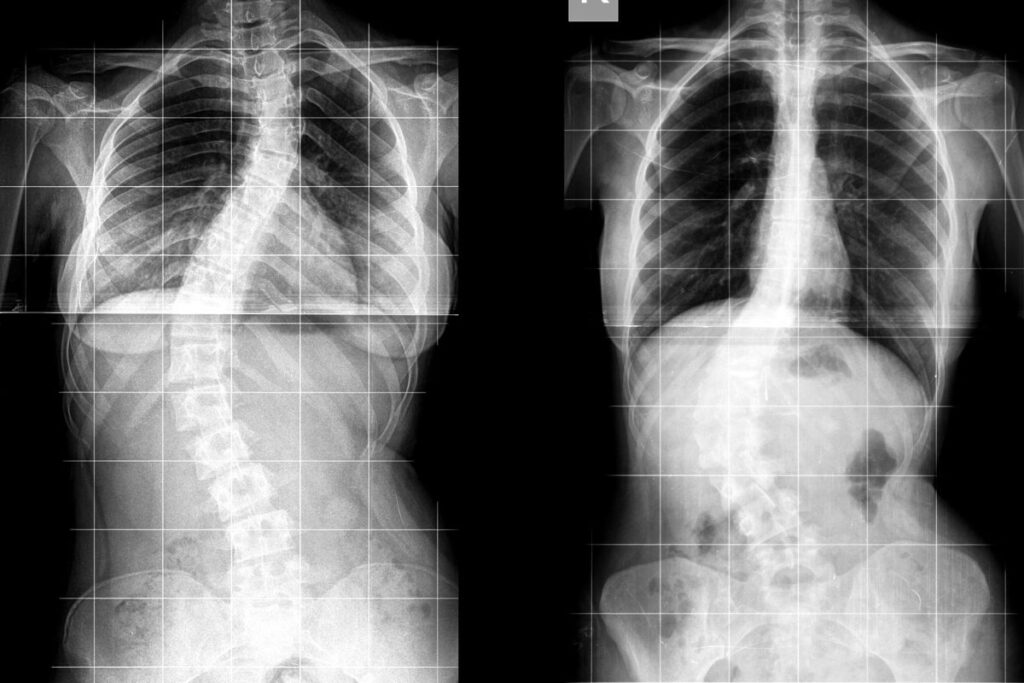

กระดูกสันหลังคด (Scoliosis) คือ ภาวะที่กระดูกสันหลังของบุคคลบิดเบี้ยวหรือโค้งไปด้านข้างมากกว่าปกติ โดยทั่วไปกระดูกสันหลังจะมีลักษณะตรงเมื่อมองจากด้านหลัง แต่ในผู้ที่เป็นโรคนี้จะเห็นว่ากระดูกสันหลังมีการเอียงเป็นรูปตัว “C” หรือ “S” ซึ่งหากไม่ได้รับการดูแลอย่างเหมาะสมอาจส่งผลกระทบต่อสุขภาพโดยรวมในระยะยาว รวมถึงการเคลื่อนไหวและอวัยวะภายในบางระบบ

กระดูกสันหลังคดเกิดจากการบิดเบี้ยวของกระดูกสันหลังในแนวด้านข้าง (Lateral curvature) โดยอาจโค้งไปด้านซ้าย หรือ ขวา และ บางครั้งมีการบิดหมุนร่วมด้วย เมื่อมองจากด้านหน้าอาจไม่เห็นความผิดปกติชัดเจน แต่เมื่อมองจากด้านหลังจะเห็นว่ากระดูกสันหลังเอียงไปข้างใดข้างหนึ่ง หรือมีไหล่สูงต่ำไม่เท่ากัน สะโพกเอียง หรือมีโหนกหลังโผล่ออกมาในบางท่าทาง

การรักษากระดูกสันหลังคดขึ้นอยู่กับ ระดับความรุนแรง ช่วงอายุ และสาเหตุของโรค โดยแพทย์จะประเมินแนวกระดูกผ่านภาพ X-ray วัดมุมโค้งที่เรียกว่า “Cobb angle” เพื่อวางแผนการรักษาที่เหมาะสม